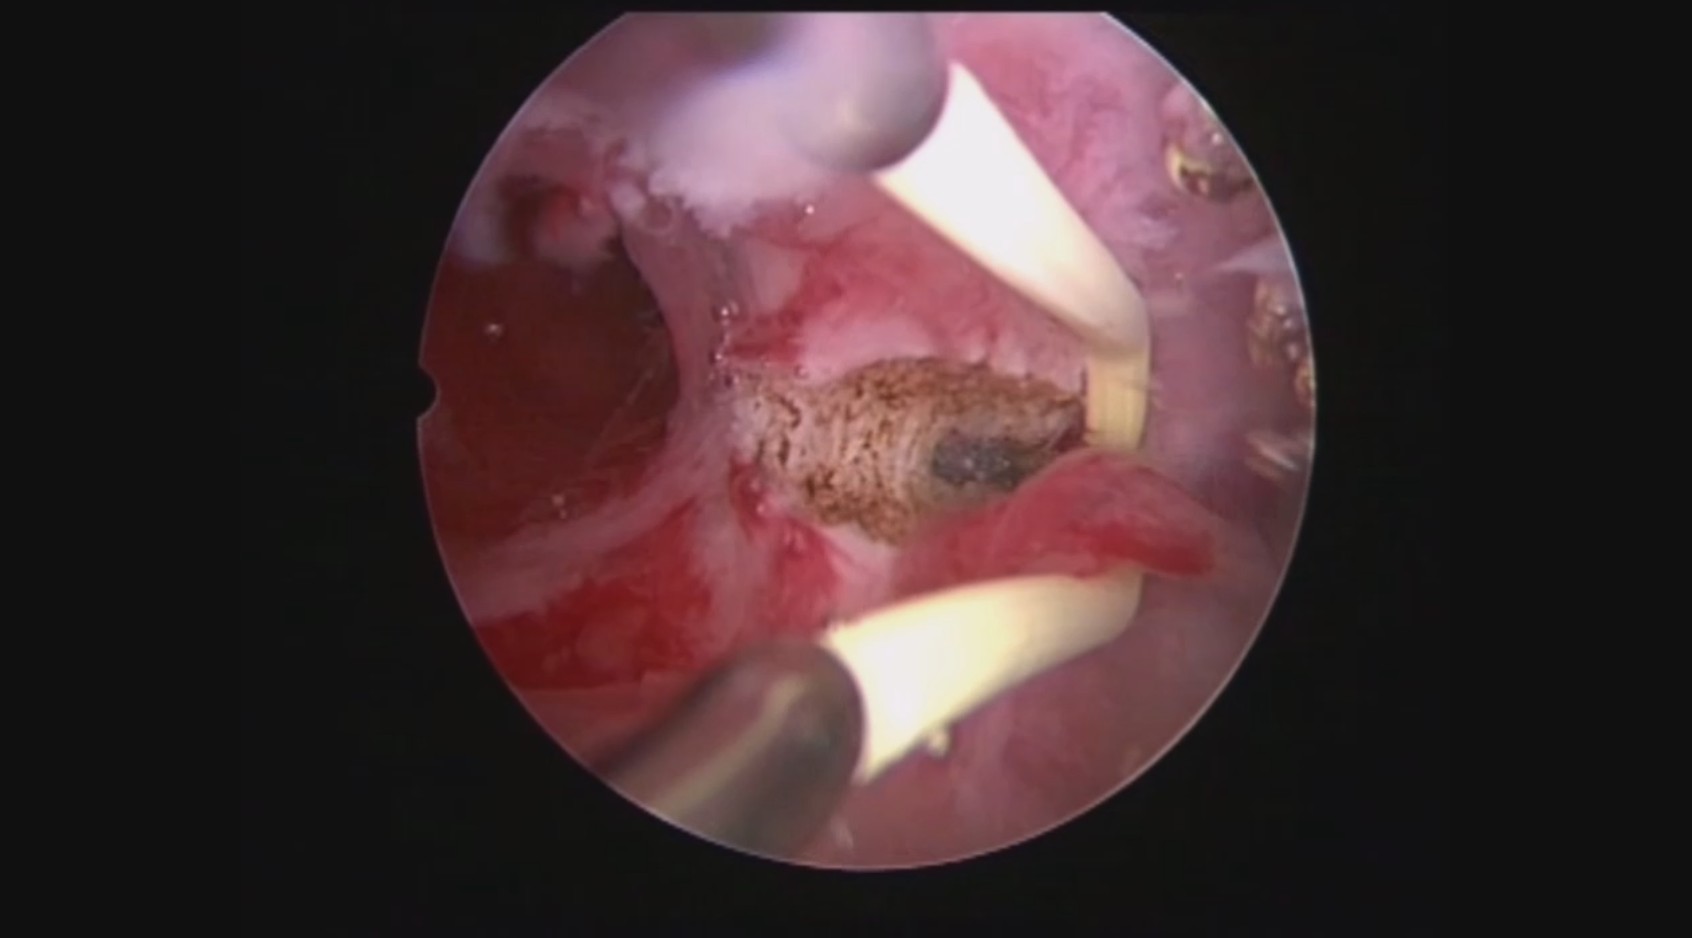

患者32岁,G6P0,继发不孕,2017年8月行宫腔镜探查,发现宫腔两侧及宫底致密粘连,尤其是宫腔右侧多重粘连,宫腔狭小。单极电切分粘,恢复宫腔形态,显露双侧输卵管开口。2018年8月自然妊娠40多天,我在兰州大学附一院生殖中心进修,病人微信发B超给我,大孕囊,胎心微弱,外院疑诊胚胎停育,拟行清宫,嘱病人不要轻易清宫,继续保胎1周,复查B超,胚胎发育正常。病人的信心和坚持成就了她自己和孩子的奇迹,孕期顺利,足月分娩。后病人再次妊娠1次,人流终止妊娠,现41岁,G8P1。